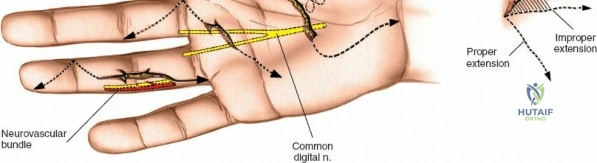

The digital neurovascular bundles (NVBs) run along the radial and ulnar sides of each digit, volar to the collateral ligaments, providing sensation and vascularity. Proper identification and protection of these bundles are paramount during any volar dissection. Proximally, the median nerve gives rise to recurrent motor branches to the thenar muscles and sensory branches to the thumb, index, middle, and radial half of the ring finger. The ulnar nerve supplies the hypothenar muscles, adductor pollicis, and interossei, along with sensory innervation to the little finger and ulnar half of the ring finger. The palmar arches (superficial and deep) provide critical vascular supply to the hand.

After marking the incision, the skin and subcutaneous tissues are carefully incised. In the digits, the triangular skin flaps created by the Bruner incision are elevated using fine skin hooks or small self-retaining retractors. Dissection should proceed in the subcutaneous plane, superficial to the digital neurovascular bundles, which run along the radial and ulnar borders of the digit, immediately adjacent to the flexor sheath.

Care must be taken to identify and protect these bundles. Any existing lacerations or hematomas are debrided. The digital nerves and vessels are carefully dissected free from the surrounding connective tissue and retracted, typically dorsally and laterally, using vessel loops or fine retractors to provide clear access to the underlying flexor sheath.

Neurovascular Bundle Management

If digital nerves or vessels are lacerated, they are repaired after tendon repair or at a separate stage depending on the complexity.

- Nerve Repair: Digital nerves are repaired primarily using microsurgical techniques (e.g., epineurial repair) with fine monofilament sutures (e.g., 8-0 to 10-0 nylon) under magnification. Tension-free repair is paramount.

- Vascular Repair: Digital arteries can be repaired with microsurgical techniques using fine sutures (e.g., 9-0 or 10-0 nylon). Ligation may be necessary if repair is not feasible, provided the contralateral digital artery provides adequate perfusion.